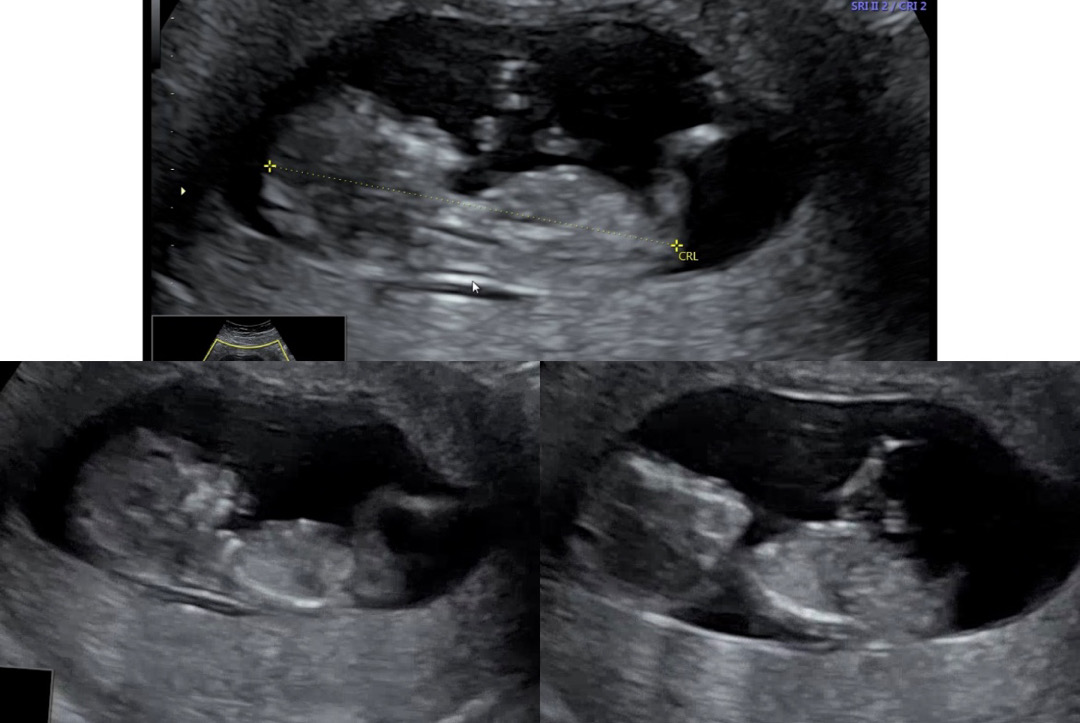

딸일까요 아들일까요? 고수님들 부탁드려요!!

12주차 초음파보고왔는데 성별 한번 봐주세요~!!!